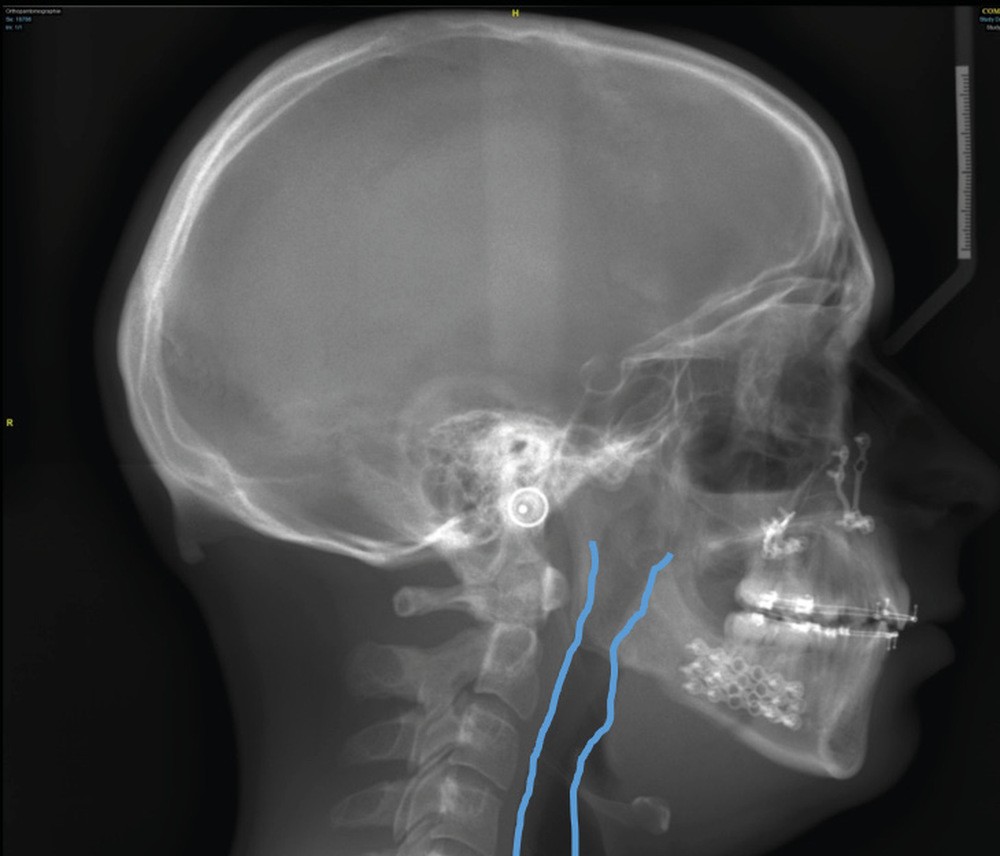

Le Dr François Cheynet et à nouveau le Pr Michel Le Gall (fig. 12) viendront plaider pour une prise en charge chirurgicale précoce de certains décalages squelettiques, afin de briser au plus vite la spirale dysmorpho-dysfonctionnelle et influencer le schéma de croissance postopératoire.

Le Dr Paul Cresseaux présentera dans un premier temps un ancrage squelettique, simple et efficace, développé par ses soins, pour optimiser la préparation orthodontique des classes II squelettiques : l’Abalakov (fig. 13a-d). Puis, il défendra la prise en charge simultanée, au cours d’un unique temps chirurgical, de l’ensemble des anomalies squelettiques présentées par nos patients.